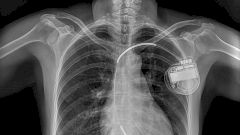

К 2009 году по всему миру ежегодно имплантировалось уже более 250 000 ИКД. Современные модели гораздо более совершеннее тех, что были в 1980-х. Они способы охватить более широкий спектр и вылечить от различных видов аритмии и как правило сочетают в одном устройстве функционал и ИКД, и кардиостимулятора. Сами электрокардиостимуляторы тоже преобразились до неузнаваемости: теперь они полностью программируемые и подстраиваются под потребности пациента, а также ведут регистрацию сердечной деятельности для ее дальнейшего анализа — данные передаются на компьютер по беспроводной связи или через Интернет.